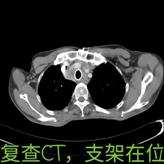

介入手术如期举行,正如吴主任所料,患者根本不能躺下,张绿秀麻醉师只能让患者坐着实施诱导麻醉,麻醉后上官主任在团队娄希贤、朱梦楚、颜晗晗等医生的协作下快速插入硬质支气管镜建立气管通道后,立即实施气道内肿瘤圈套切除术,术中患者血氧饱和度一度下降,在打通一条细小通道后立即置入导丝,成功放置一个覆膜支架,支架释放后患者血氧饱和度立即上升,手术取得圆满成功。

手术后当天患者就能平卧睡觉,第2天就能下床活动。之后转放疗科完成放疗后,患者病情得到了有效的控制,已经能够活动自如,目前已经平安出院,即将回到回到阔别已经的安徽老家。